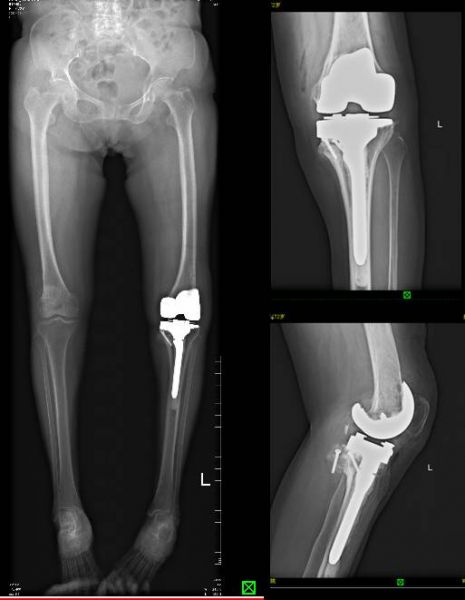

术后X片

在排除手术禁忌症,积极完善相关术前准备后,由赵峻主任医师带领其团队为张某制定了详细的术前规划,成功实施了左膝人工关节置换术。患者胫骨内侧平台严重塌陷骨缺损,手术中使用了胫骨平台垫块仍然残十多毫米厚度的骨缺损,赵峻主任“巧妙”地将术中截骨出来的股骨髁废物再利用,修整后移植到胫骨平台缺损处完美解决了手术障碍,开创性地使用了骨移植技术解决了困难。

术后患者关节畸形得到明显纠正,疼痛得到有效缓解,活动度也明显改善。整个围手术期贯彻快速康复理念,术后第二天患者便可借助助行器独自行走,无任何神经受累症状。手术后一个月复查时,张某已经可以脱拐行走。患者表示自己赶上了好时代,感谢政府精准扶贫政策助力,感谢州医院骨一科医护团队。